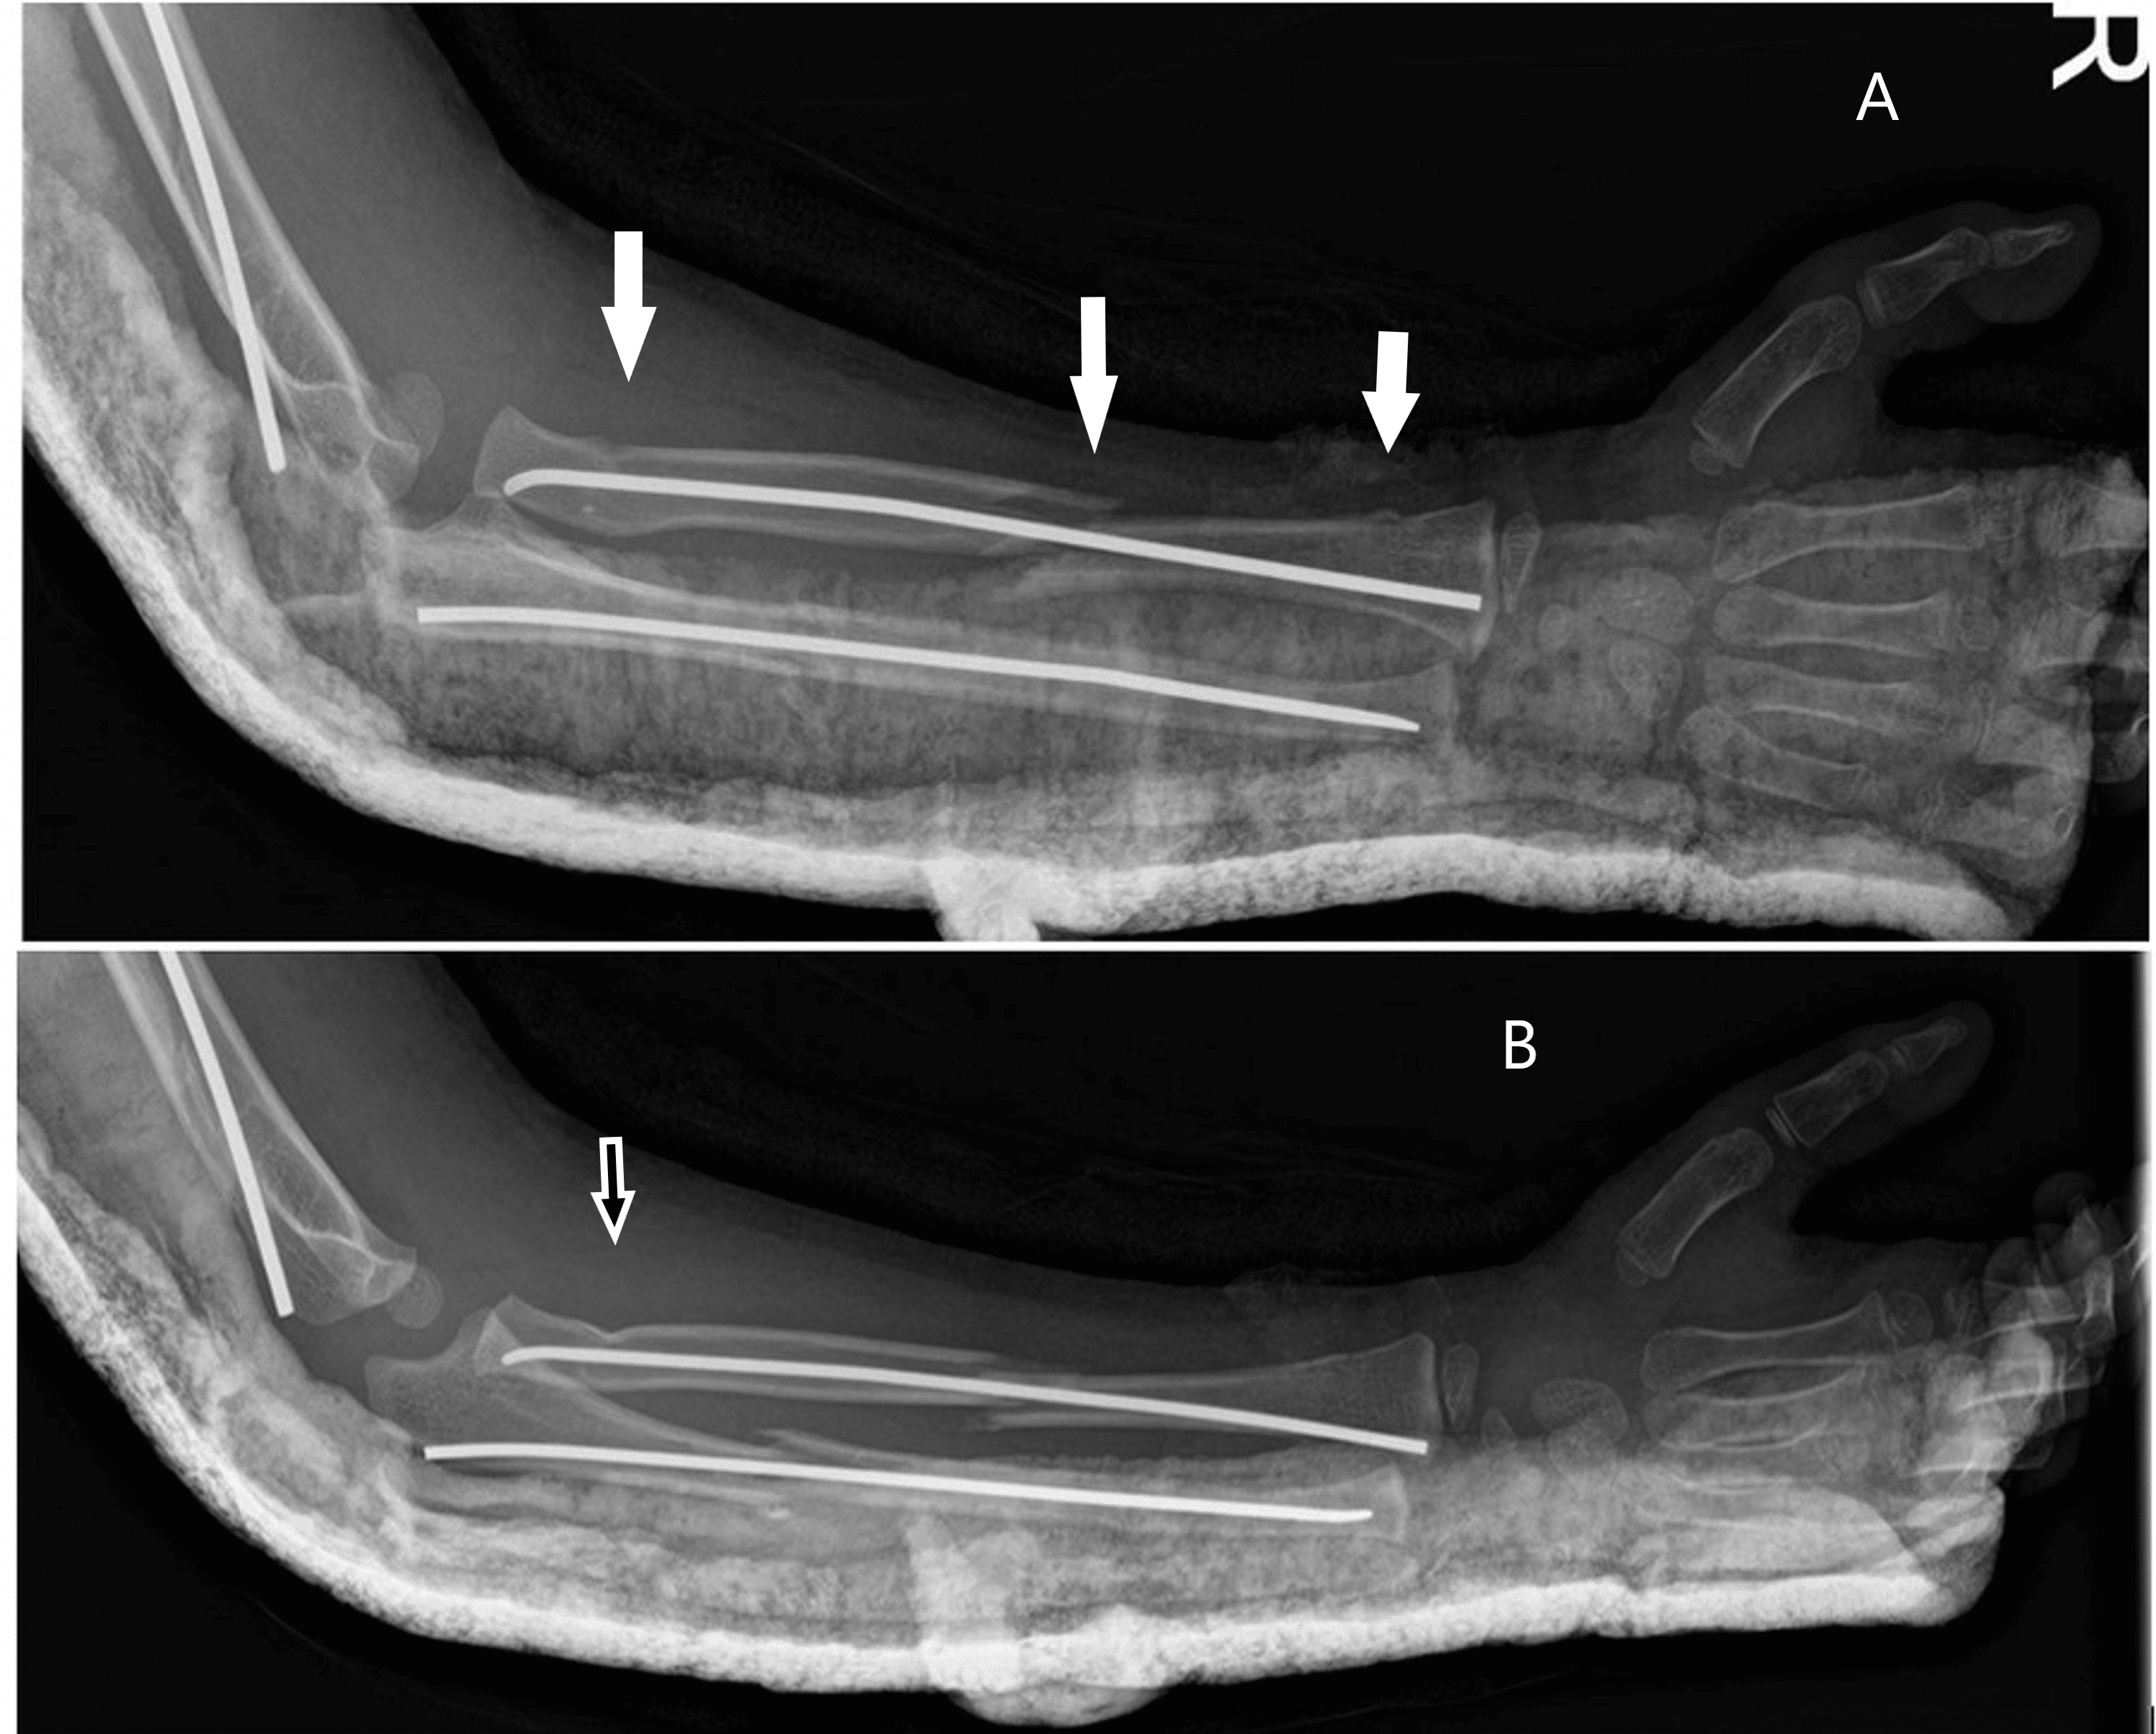

(PDF) Floating Dislocated Elbow A Variant with Articular Fracture of Floating Elbow Definition Floating elbow fractures in adults are rare and complex injuries with unpredictable outcomes. Stanitski and micheli firstly used the term “floating elbow” to describe ipsilateral humerus fracture combined with forearm. The present study was designed to. The term floating elbow was first introduced by stanitski and micheli to describe an injury pattern in children involving concomitant. The current knowledge regarding. Floating Elbow Definition.